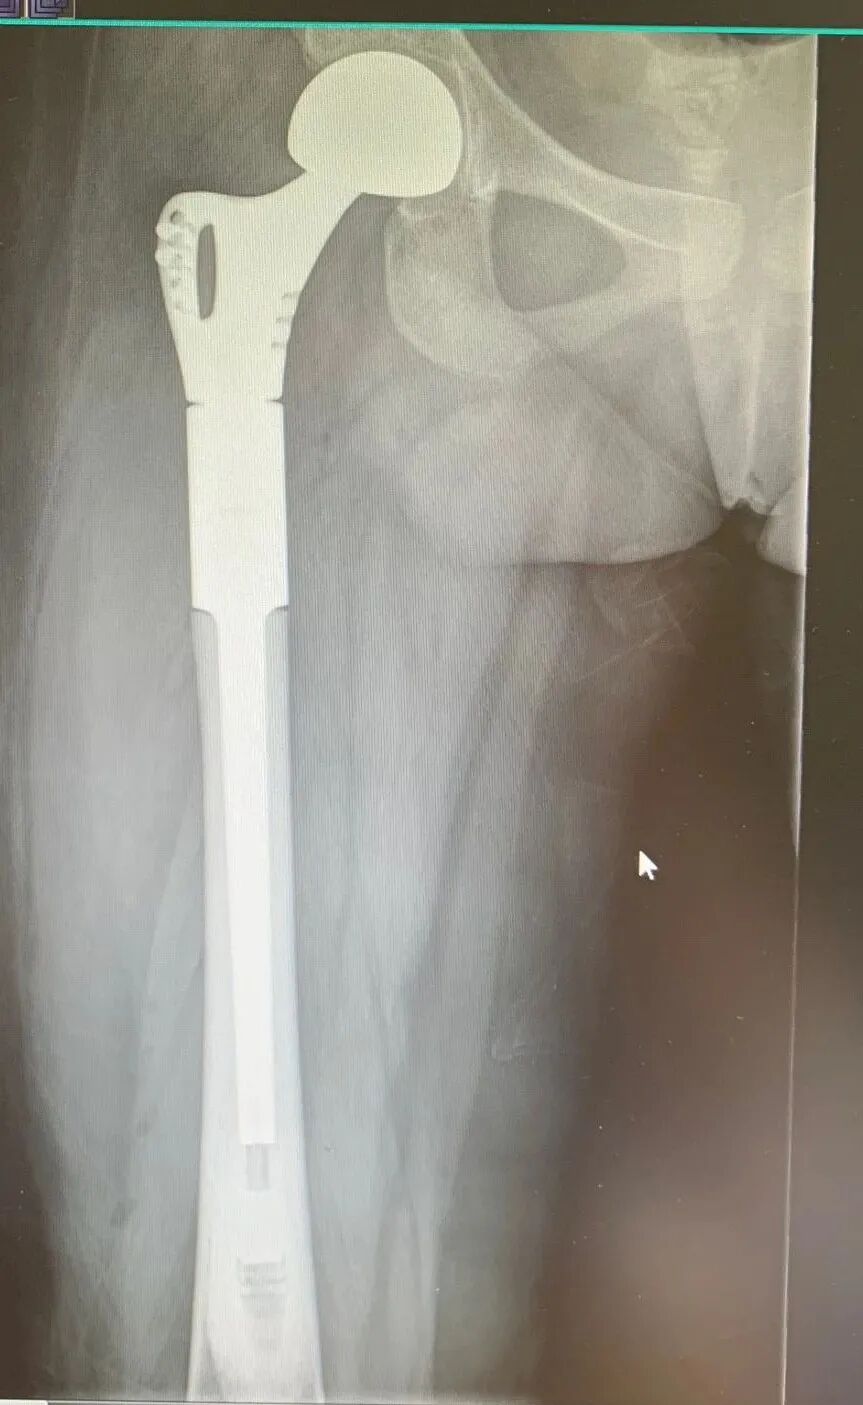

骨肿瘤康复治疗组早期介入股骨大段髋置换、膝关节肿瘤假体置换、半骨盆置换、全椎体置换等复杂骨肿瘤术后,在缓解症状同时改善患者的各项功能,维护患者的生命尊严。

关节外科康复治疗组保证了髋膝关节置换术后患者可在术后第二天下地行走,为完成48小时日间髋关节置换术的快速康复奠定了良好基础。目前进一步配合骨科推进48小时日间膝关节置换术快速康复管理。

髋关节置换术后24小时内下地